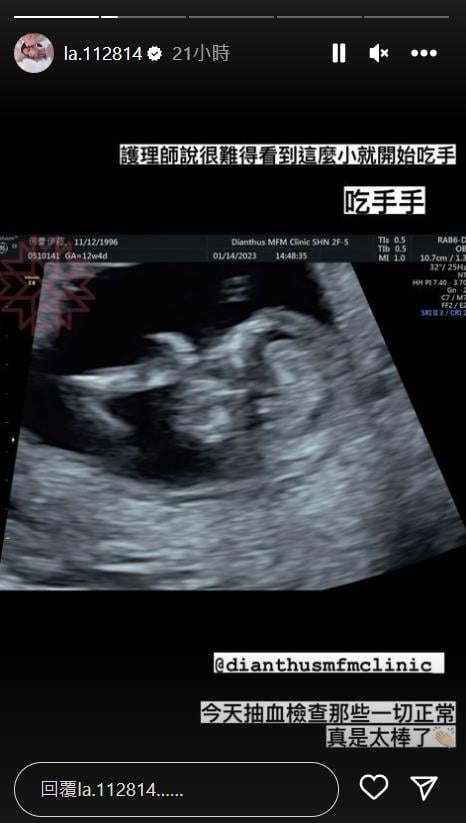

蕾菈自從向外界宣布懷上二寶後,就非常頻繁更新自己IG的「懷孕小蕾」動態,上禮拜老公還開始學習幫她的肚子按摩、擦妊娠霜油,夫妻互動羨煞眾人;14日下午蕾菈還PO出最新產檢照,從超音波圖中可見,胎兒的頭部明顯在右側,而且還把手放在嘴巴裡,就連護理師都驚訝地說:「很難得看到這麼小就開始吃手,吃手手!」蕾菈還透露當天有做了抽血檢查,結果一切正常,事情彷彿全都在往正面發展,讓她也忍不住拍手高喊:「真是太棒了!」